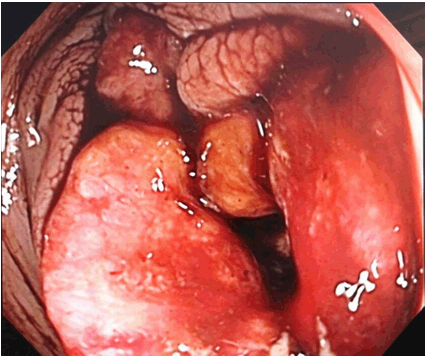

A 61-year-old male arrived at our emergency department complaining of abdominal pain for the last 30 days. The pain was poorly localized and characterized. It worsened in the 24 hours prior to seeking medical care. Patient was also complaining of chronic bloody diarrhea, mostly melena. Had only one episode of bright red blood per rectum, and one episode of vomit (digested food with no blood), both occurring in the 24 hours prior to seeking medical care. Patient uses ethanol and tobacco chronically. He was admitted for investigation. On admission laboratory examinations showed hemoglobin 3.5 g/dl and hematocrit 11.2%. The patient was immediately submitted to blood transfusion. During hospitalization, abdominal computed tomography scan showed situs inversus with signs of dextrocardia, an expansive, concentric and mucosal lesion located in the gastric antrum, left urinary tract calculus and left hydronephrosis (Figure 1). The first upper endoscopy showed an infiltrative lesion in the gastric antrum. The patient presented hematemesis followed by hemodynamic decompensation eight days after upper endoscopy. He was resubmitted to an upper endoscopy, which revealed a gastrocolic fistula, and was maintained with a nasogastric tube draining fecaloid secretion. Gastric infiltrative lesion was biopsied in the first upper endoscopy; the results were released nine days later and showed an ulcerated and well differentiated adenocarcinoma of the gastric antrum, with tubular pattern. Colonoscopy revealed an infiltrative and circumferential lesion in the transverse colon, occupying 90% of its lumen (Figure 2). After diagnostic investigation, patient was submitted to resection of the gastric antrum, cecum, ascendant colon and transverse colon – 2/3 of its extension (Figure 3A-B). It was made an anastomosis between the terminal ileum and the distal transverse colon, and a Roux-en-Y anastomosis to connect stomach and intestine (Figure 4). The patient presented good recovery in the postoperative period. Histopathologic examination of the resected portion showed adenocarcinoma of the transverse colon penetrating the gastric wall, and gastritis. Two out of twelve examined lymph nodes from the surrounding fat tissue were affected. Postoperative histopathology did not show adenocarcinoma of the gastric antrum.

Figure 2: Colonoscopy showing a circumferential lesion at the transverse colon, occupying 90% of its lumen.